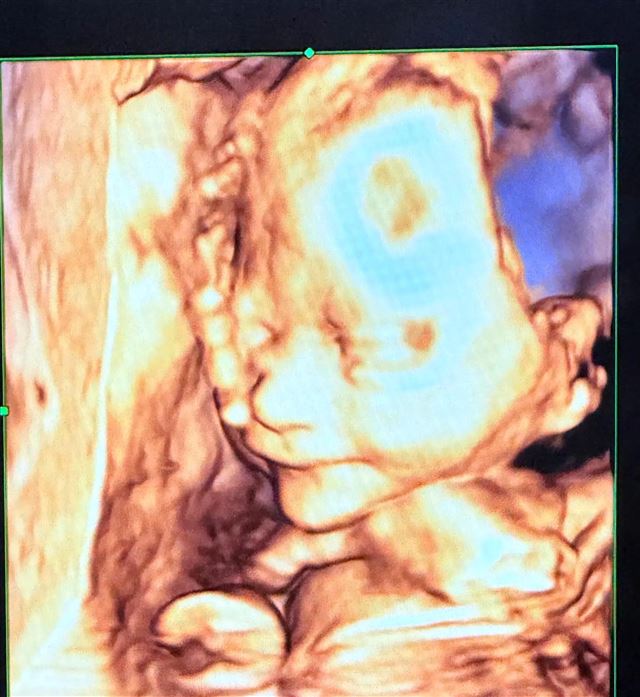

在曝光的四维彩超影像中,清晰呈现了胎儿握拳打哈欠的动态画面,网友们纷纷留言:“鼻梁高挺遗传了包贝尔”、“睫毛投影好优越”。